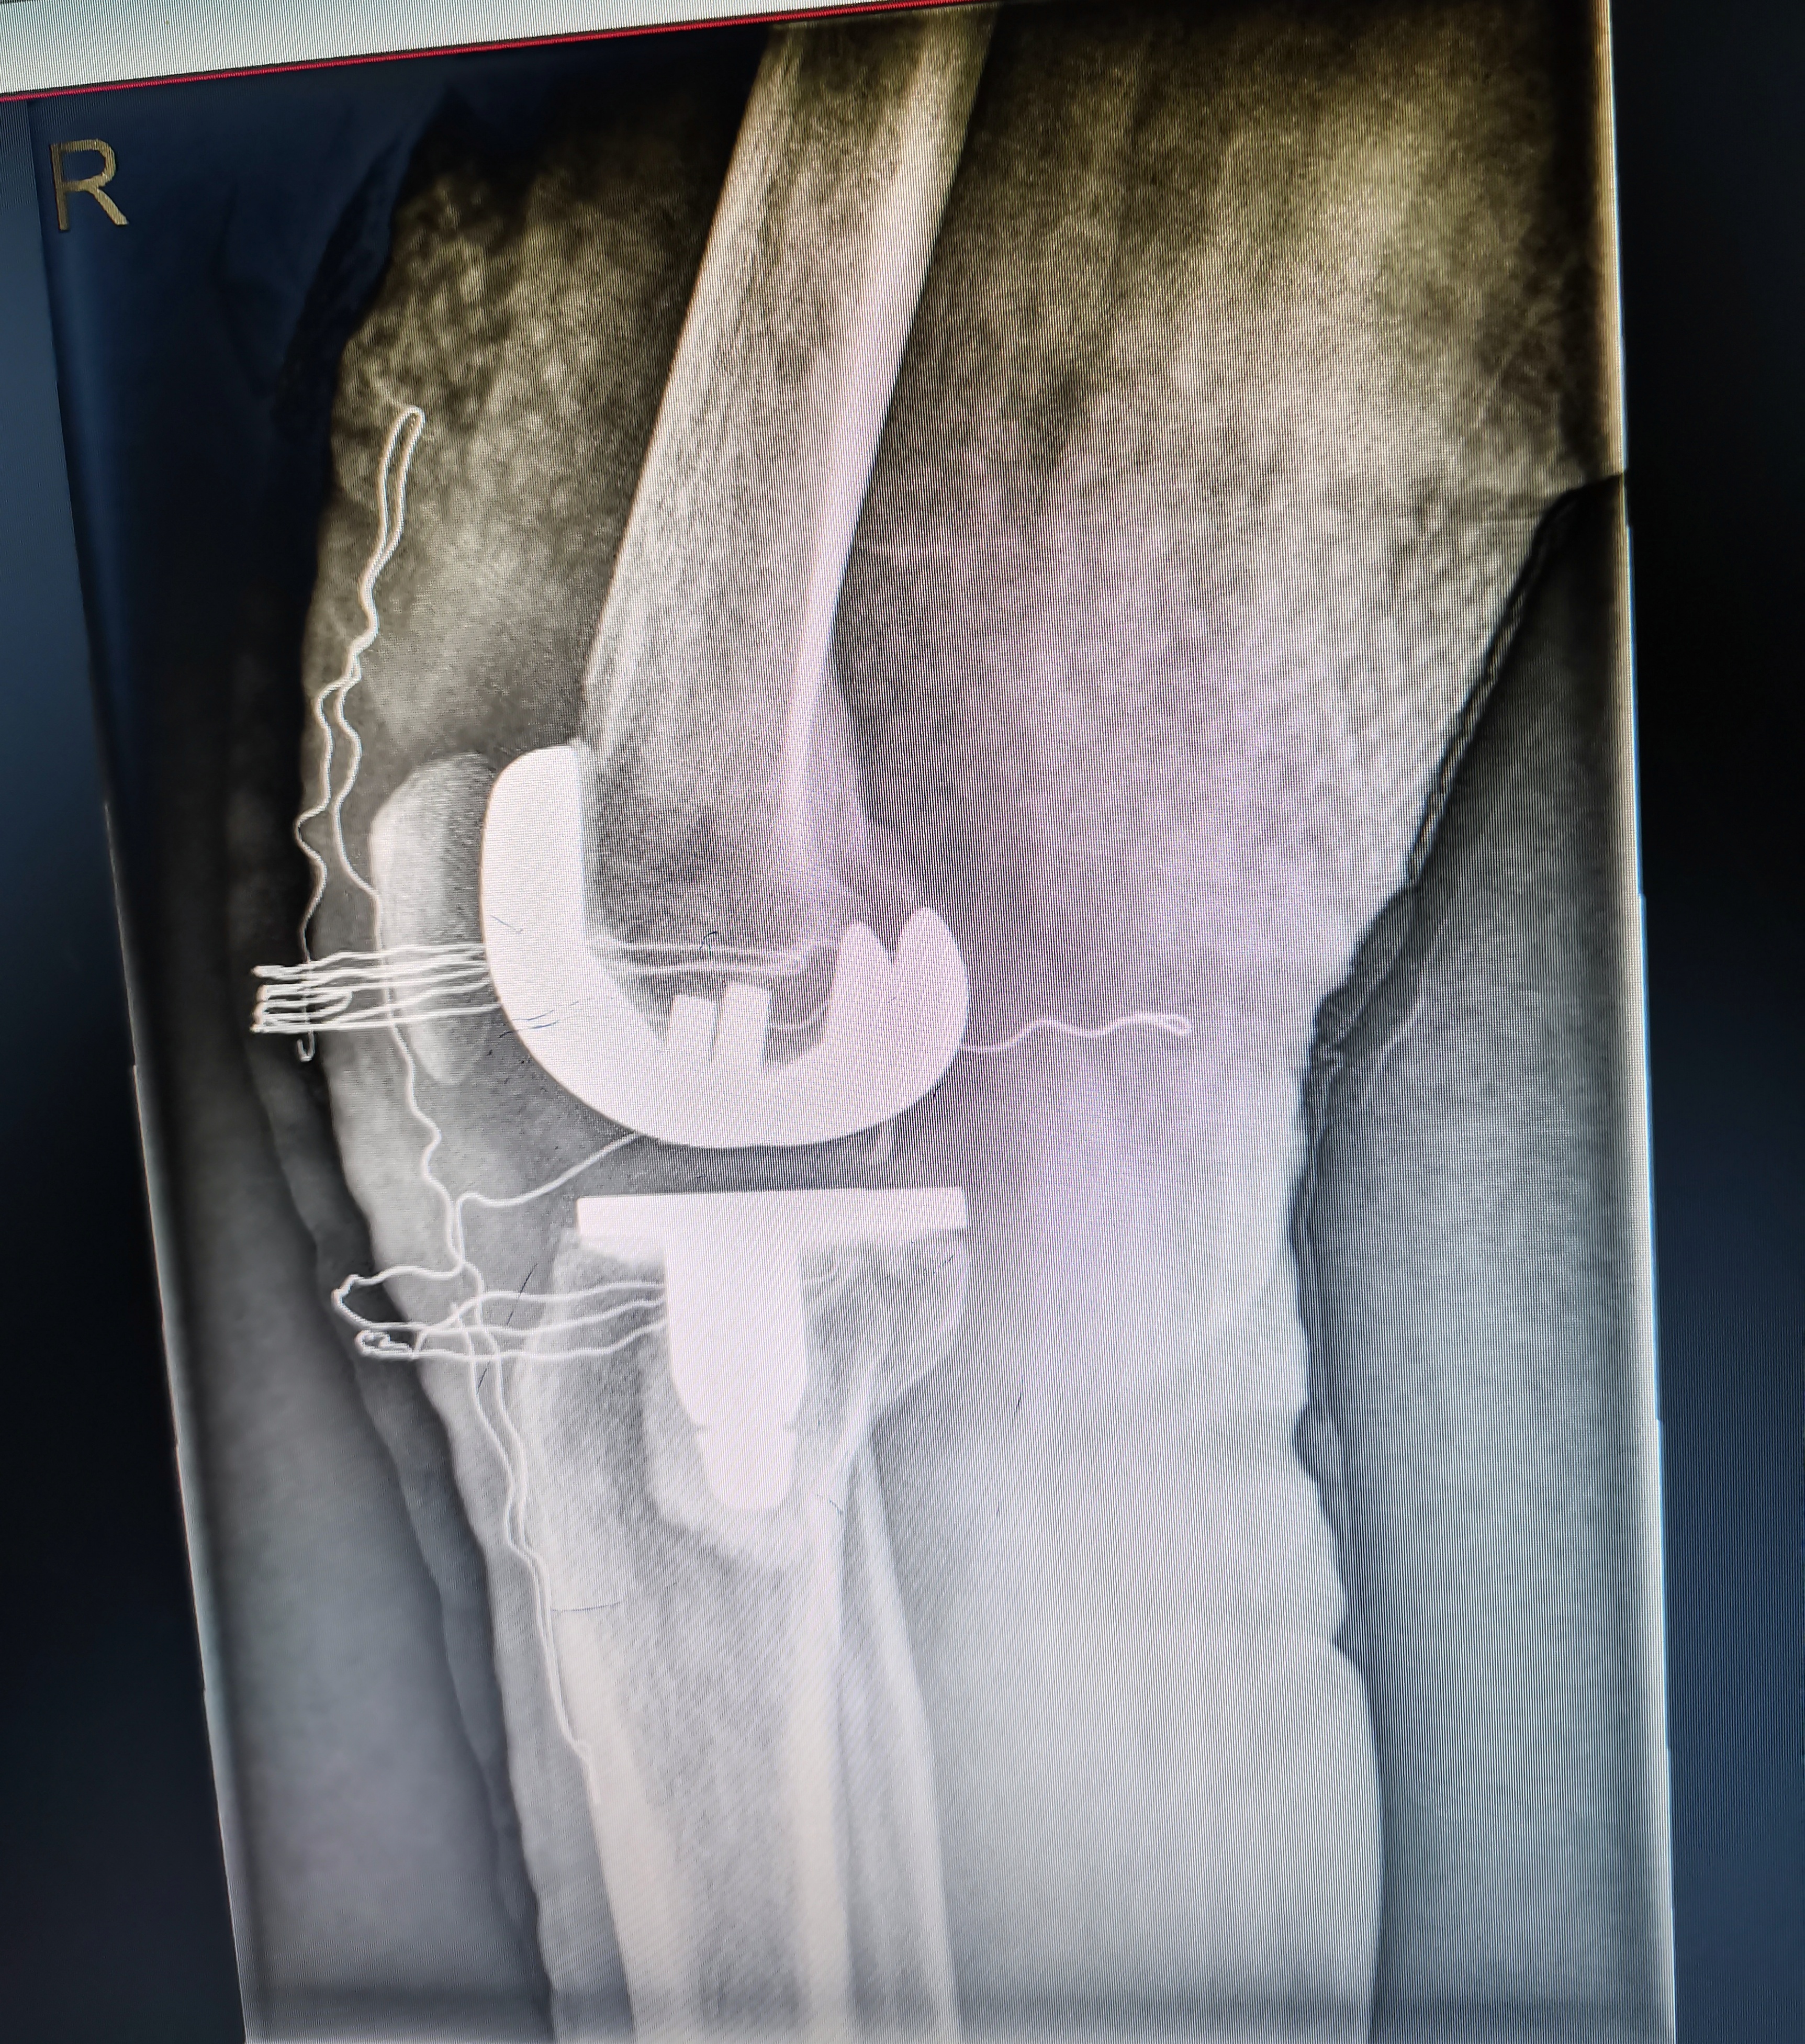

術(shù)中照片

術(shù)后照片